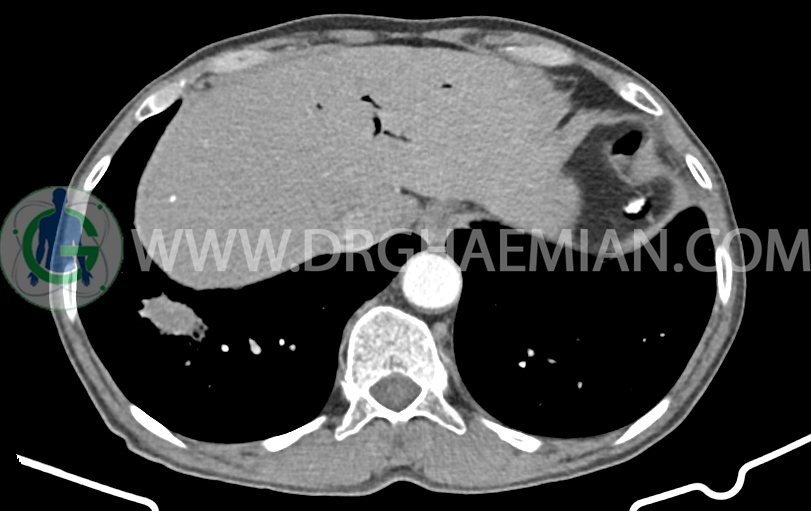

شواهد جراحی ویپل به صورت partial pancratectomy و کوله سیستکتومی و همچنین گاستروژژنوستومی و پانکراتیکوژژنوستومی – هپاتوژژنوستومی مشهود است .

MPD دیلاته به قطر 8mm (حاوی استنت می باشد)

body پانکراس کمی کوچک و اتروفیک است